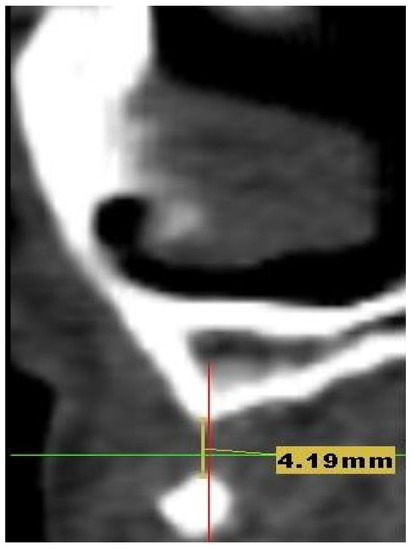

Customized 3D-Printed Titanium Mesh Developed for an Aesthetic Zone to Regenerate a Complex Bone Defect Resulting after a Deficient Odontectomy: A Case Report

Background and Objectives: Alveolar ridge augmentation in the complex bone defect is a popular topic in implantology. Guided bone regeneration (GBR) is one of the most commonly applied methods to reconstruct alveolar bone. The application of a membrane is the fundamental principle of GBR. There are many membrane types used in oral surgery, but the advantage of the titanium mesh is the rigidity which provides space maintenance and prevents contour collapse. The smooth surface also reduces bacterial contamination. Using computer-aided design (CAD) and computer-aided manufacturing (CAM) in dentistry allows us to obtain the perfect architecture form of the mesh, which covers and protects the bone reconstruction. Case presentation: We present a surgical case of a 27-year-old female patient with severe aesthetic bone atrophy after a deficient odontectomy. Based on the GBR clinical applications, the technique consists of bone reconstruction and a customized titanium mesh application. Using mesh titanium in this case presentation was a reliable alternative to perform a lateral alveolar bone augmentation and reconstruct ridge deformities before reaching an ideal implant placement. Conclusions: According to our case report, the customized titanium mesh could be a valuable option for guided bone regeneration in aesthetic maxillary defects. Full article